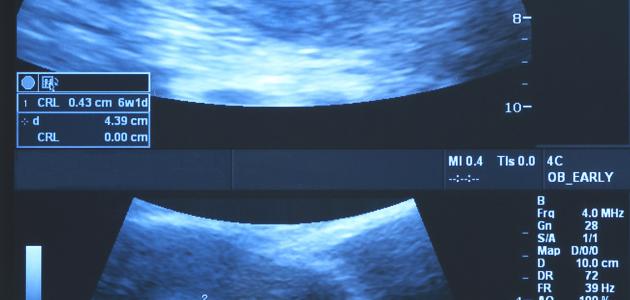

تختلف أعراض الحمل بين امرأة وأخرى، كما يختلف وقت ظهور أعراض الحمل بين امرأة وأخرى؛ فهناك من تظهر عليهنّ أولى علامات الحمل بعده بأسبوع إلى أسبوعين منه، لكن هناك من لا يشعرن بأيّة أعراض خلال الأشهر القليلة الأولى.[١]

تُصنّف أعراض الحمل في الشّهر الأوّل كما يأتي:[٢][٣]